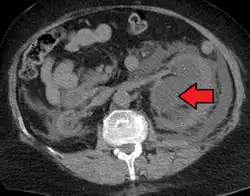

CT scan of bilateral hydronephrosis due to a bladder cancer -

Massive hydronephrosis as marked by the arrow. -